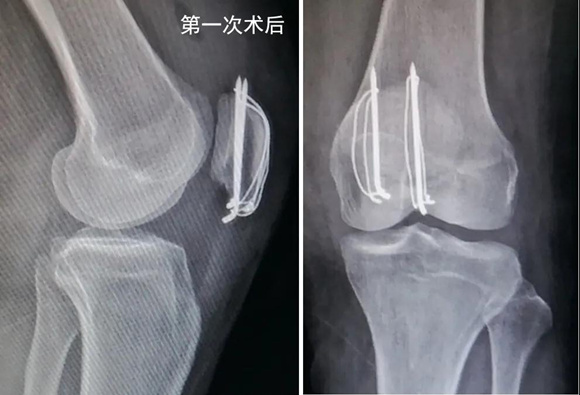

洪女士特意选择当地有名的医院,请骨科主任给她做了切开复位加经典的钢丝克氏针内固定手术。手术很顺利,术后片子显示骨折复位和内固定物位置满意(如下图)。